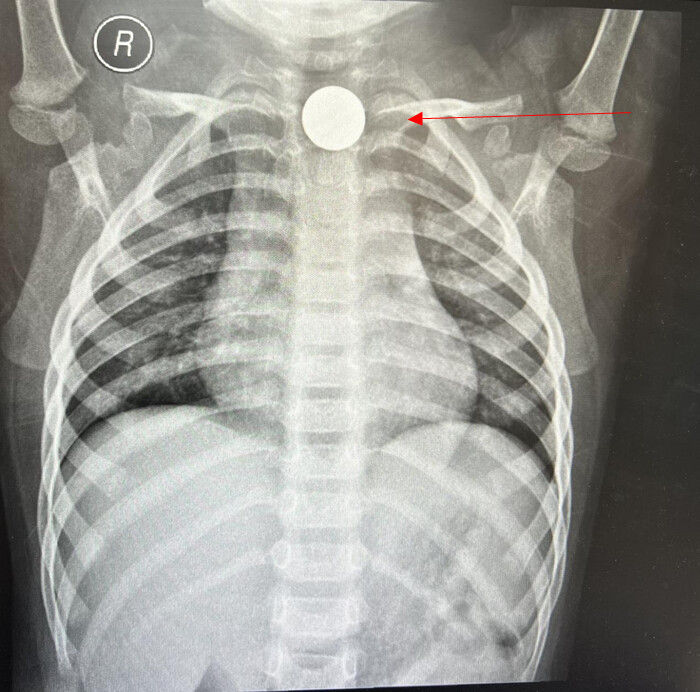

据家长描述,孩子在玩耍时不慎将一枚硬币吞入,在当地医院检查发现异物已卡压于食管上端第一狭窄处,因病情紧急,建议转入安医大四附院(附属巢湖医院)院救治。到达医院后,患儿因不适持续哭闹不止,若异物长时间滞留,可能引发食管黏膜损伤、感染,甚至穿孔或大出血,严重威胁生命。

手术中,消化内科二病区副主任医师陆宗海凭借丰富的经验,在水肿的食管黏膜环境中精准定位硬币,用异物钳调整角度轻柔夹住异物,沿食管弧度缓慢退镜,仅用3分钟便将硬币完整取出,术后患儿留院观察一天后顺利出院。